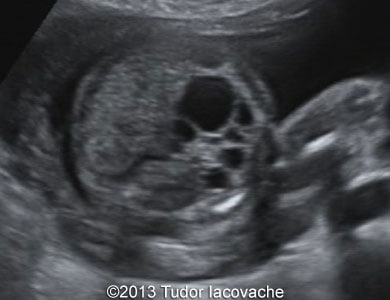

The patient was a 28-year-old primigravida. Fetal hydronephrosis with dilated renal pelvis and calices of the left kidney was noticed at 17 weeks. At 23 weeks the left kidney showed signs of multicystic dysplasia - the enlarged kidney consisted of isolated multiple cysts of various sizes. At 29 weeks the finding was even more striking. The right kidney was normal throughout the pregnancy. The multicystic dysplastic kidney was confirmed after birth.

Images 1, 2, and video 1: 17 weeks of gestation.